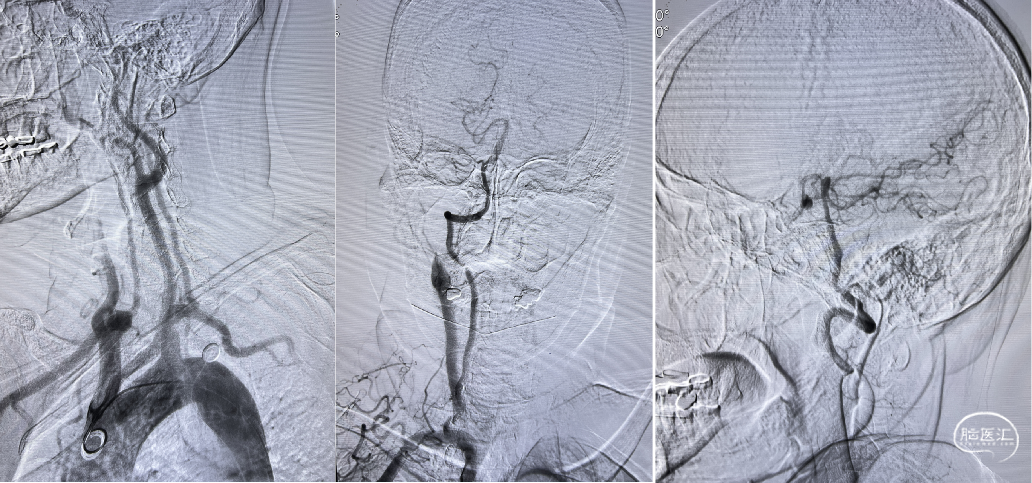

脑血管造影:3型主动脉弓,右侧颈内动脉起始段闭塞,后循环及左侧颈内动脉均未向左侧颈内动脉供血区代偿。

3型主动脉弓,用Mani管超选至右颈总动脉,用260cm加硬泥鳅导丝交换出,在泥鳅导丝导引下,用125cm的多功能管将6F Infinity长鞘置于右颈总动脉,提供稳定支撑。

在Synchro2微导丝及微导管引导下,Catalyst7抽吸导管顺利到达颈内动脉末端。

Catalyst 7抽出大量负荷血栓,大脑中动脉上干仍未显影。

微导丝微导管超选至大脑中动脉上干,微导管造影确认在血管内真腔内,释放Solitaire 4×20mm。

Solitaire 4×20mm支架锚定Catalyst 7抽吸导管到达M1段,抽吸导管负压,拉出取栓支架,取栓过程中Catalyst 7维持稳定。

两次支架取栓取栓取出血栓,血管再通。